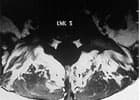

Das unten abgebildete Kernspin zeigt gesunde Rückenstrecker. Die fettige Degeneration der Rückenstrecker bei der Patientin ist in der Tat ein krasser Fall. Etwa 60% des Muskelquerschnittes der Patientin ist verfettet. Hier ist nicht mehr viel Kraft da, welche die WS stabilisieren kann.

Die abgebildete Verfettung ist sicher ein Extremfall. Nicht jedes Kernspin sieht so aus. Aber Extremfälle schärfen das Verständnis für das Prinzip:

Schwache Muskeln – fehlende Stabilität – Schmerzen